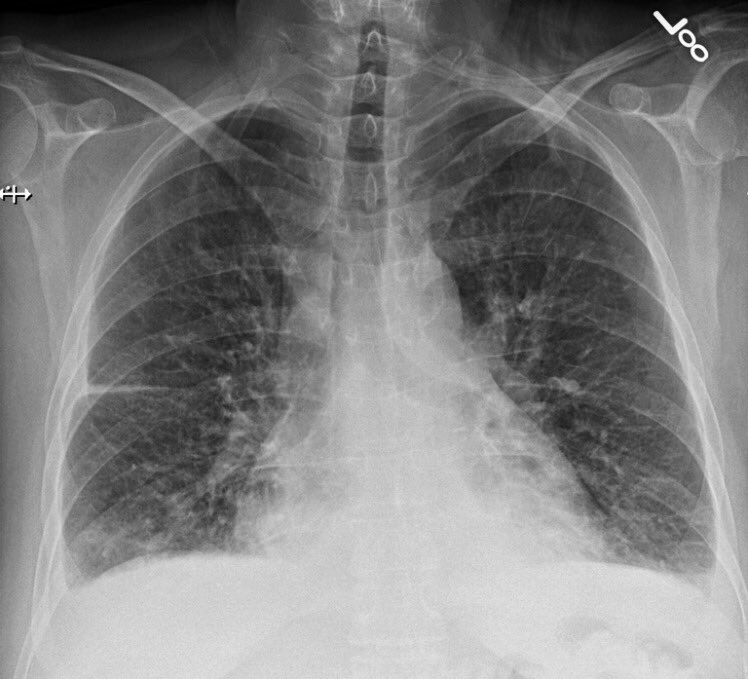

A 68 y o male with type-2 DM, CAD, CCF (EF~35%), PAD, and history of gouty arthritis presented with dyspnea and LL edema.